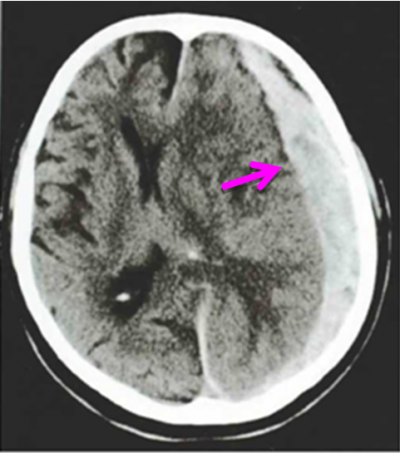

המטומה סובדורלית כרונית היא זו המאובחנת כעבור שבועיים ויותר מהחבלה. לעיתים החולים והמשפחה שכחו את האירוע החבלתי והחולה מפתח תמונה של דמנציה חדה. כאבי ראש שכיחים וכן סמני צד נוירולוגים. המטומות כרוניות שכיחות בתינוקות ובמבוגרים מעל גיל 60. ההתפתחות ההדרגתית ואיטית של התסמינים גורמת פעמים לחשיבה מוטעית שמדובר בחולה עם תסמינים על רקע נפשי וחלקם מופנים לטיפול פסיכיאטרי. המטומה כרונית ב-20% היא דו-צדדית ומודגמת טוב ב- CT או MRI (תצלום 2.16). הניקוז של ההמטומות הללו יכול להתבצע דרך חורים בגולגולת ובדורה המאפשרים פתח ניקוז ושאיבה של ההמטומה שעברה ברוב החולים התנזלות.